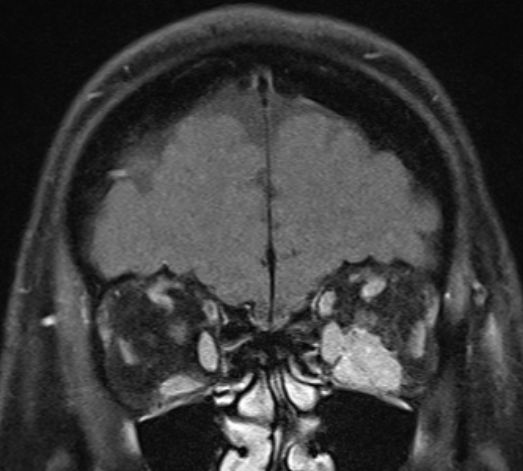

MRT eines retroorbitalen Lymphoms |